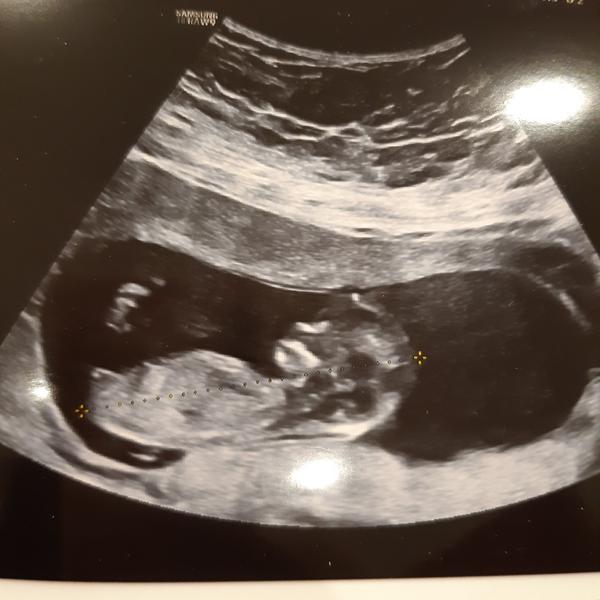

@sebinka123 tady z toho by to šlo poznat? 😁

@hawah 1 to má nějaké mazle a 2,3 typuju kluky

@sebinka123 👍 první dva kluci a třetí nejspíš bude taky, se brzo uvidí 😁

@30bar holka dle hrbolku.